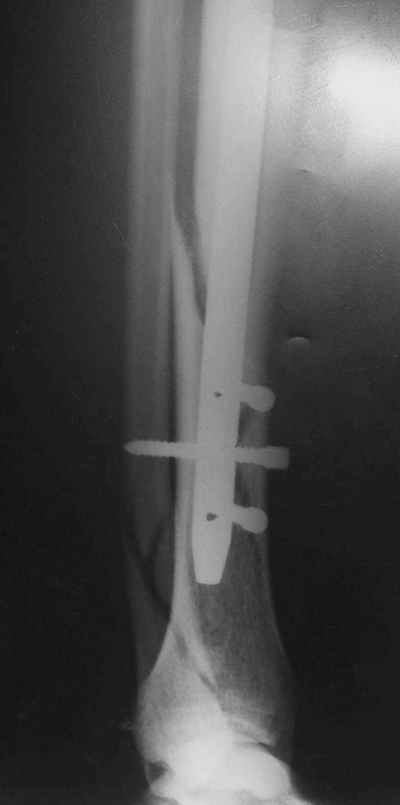

Потекло через месяц - открылось 2 свища по старому рубцу от давно удаленной пластины. На фоне гноя раза три завинчивал обратно винты, которые вылезали латерально, прямо через свищ. Потом таки провел дополнительно винты мимо гвоздя, и убрал вверху статический винт. Острый гнойный процесс стих, свищи мыла она дома дважды в день водным хлоргексидином, ходила с возрастающей нагрузкой, а к 10 мес. и свищи закрылись, и срослось. Итоговые снимки от 18 апреля 2003 г. прилагаю.

Рентгенограмы

Не удается отправить первичные снимки. А что скажите по имеющимся?!

Выполненный остосинтез нестабилен. Штифт надо заменить по "размеру" на солидный, дистльно три запирающих винта. Успехов!

Отправитель: Alexander Chelnokov 21 Январь 2005, 21:31

Перелом спиральный, то есть низкоэнергетический, так что со сращением дело обстоит уже неплохо, лишь бы "костоеда" не развилась. Отломки выглядят уже стабилизированными костной мозолью, так что довводить винты, наверно, уже незачем. Разве что при клинической оценке подвижность еще есть - тогда можно для стабилизации наложить простейший аппарат, не опасаясь контакта его элементов с гвоздем, поскольку места в дистальном метафизе оставлено более чем достаточно.